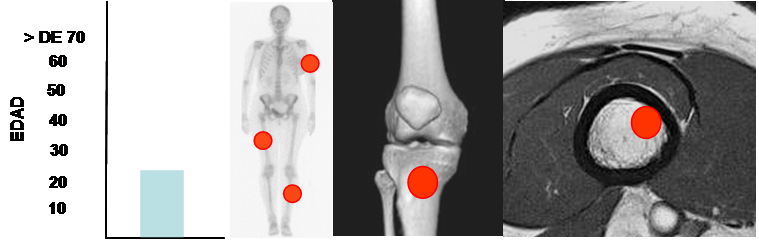

Fig 74. Osteocondroma.

Aparece en pacientes menores de 25 años. Predominio en los huesos largos.

Lesión metafisiaria, de ubicación excéntrica.

Ocurre en niños y adultos jóvenes, antes de los 25 años. (18, 20).

Tienen localización excéntrica y metafisiaria por su relación con la placa de crecimiento y predominio en las extremidades inferiores (alrededor de la rodilla) y el húmero. (18,19, 20). (Fig 74).